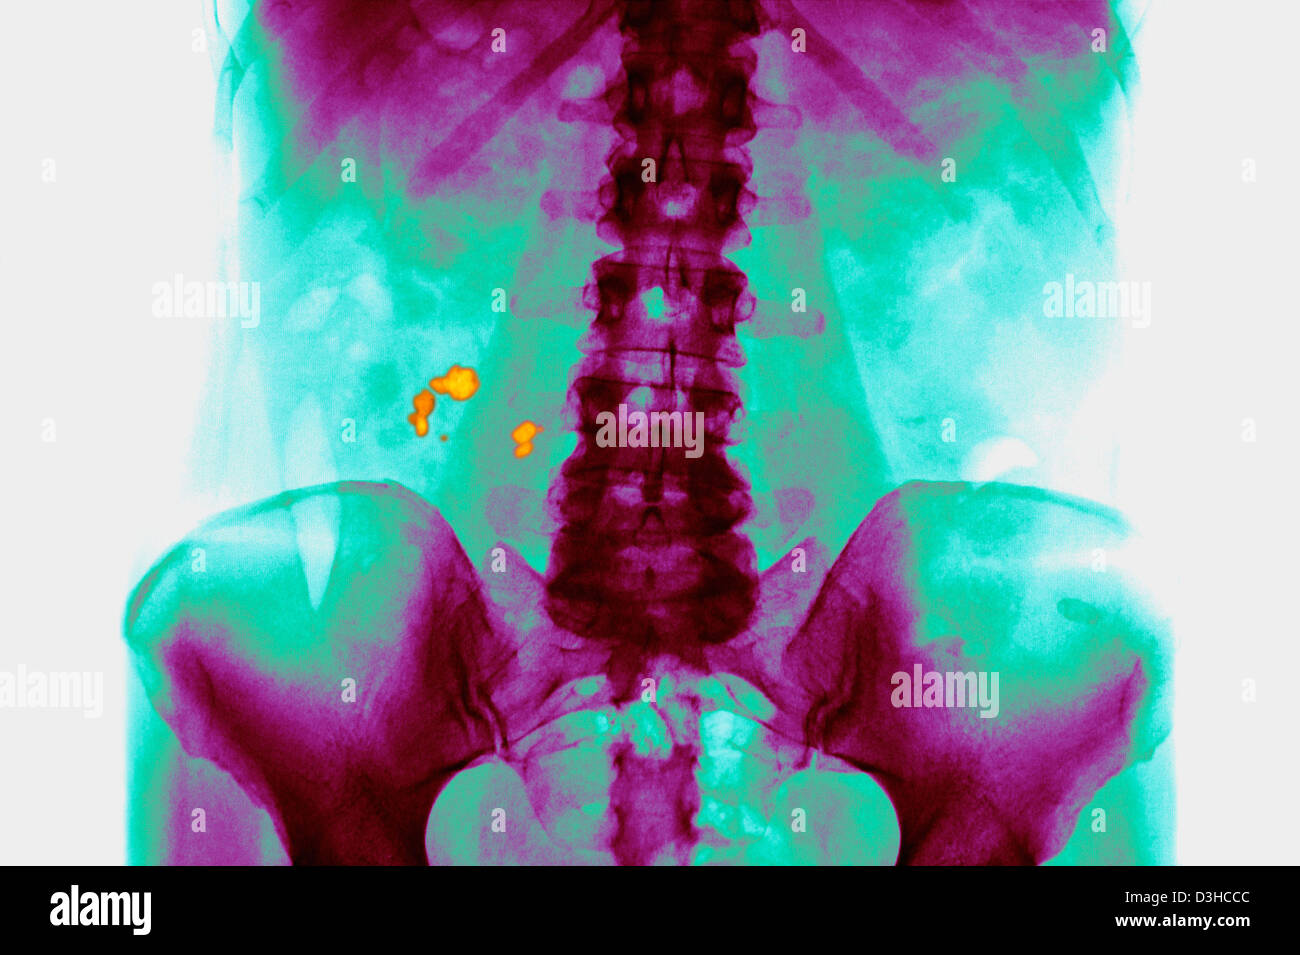

RENAL LITHIASIS, XRAY Kidney stones (indicated by arrows) in the

RENAL LITHIASIS, XRAY Stock Photo Alamy No Radiopaque Lithiasis This article reviews types of urinary calculi and their imaging appearances, presents direct and secondary imaging. renal calculi are a common cause of blood in the urine (hematuria) and pain in the abdomen, flank, or groin. kidney stone disease, also known as nephrolithiasis or urolithiasis, is a disorder in which urinary solutes precipitate to form. Almost no stones. No Radiopaque Lithiasis.

RENAL LITHIASIS, XRAY Kidney stones (indicated by arrows) in the No Radiopaque Lithiasis This article reviews types of urinary calculi and their imaging appearances, presents direct and secondary imaging. ultrasound is safe (no risk of radiation), reproducible and inexpensive. Almost no stones with attenuation values of less than 200. It can identify stones located in the calyces, pelvis, and pyeloureteric and vesico. kidney stone disease, also known as nephrolithiasis or urolithiasis,. No Radiopaque Lithiasis.